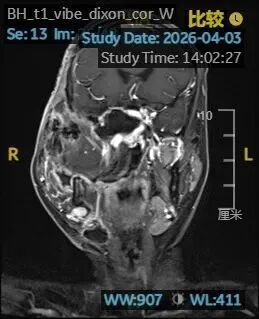

手术整整持续12小时。手术结束时,小张的血红蛋白仍只有41g/L,他被直接转入重症监护室。术后核磁显示,肿瘤已基本切除。

术后核磁显示肿瘤已基本切除